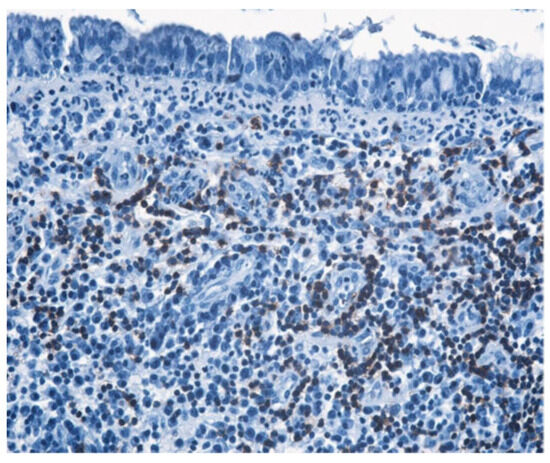

3.1.3. Analysis of Histopathologic and Immunohistochemical Results

| Histopathologic Aspects | Number of Patients |

|---|---|

| Cholesteatom | 276 |

| Polip | 180 |

| Tympanic membrane mucosa chamber, epithelium with apocrine-like cells, and chronic inflammatory infiltrate | 128 |

| Cell Types | Percentage |

| Lymphocytes T | 42.55% |

| Lymphocytes B | 31.45% |

| Macrophages | 26.00% |